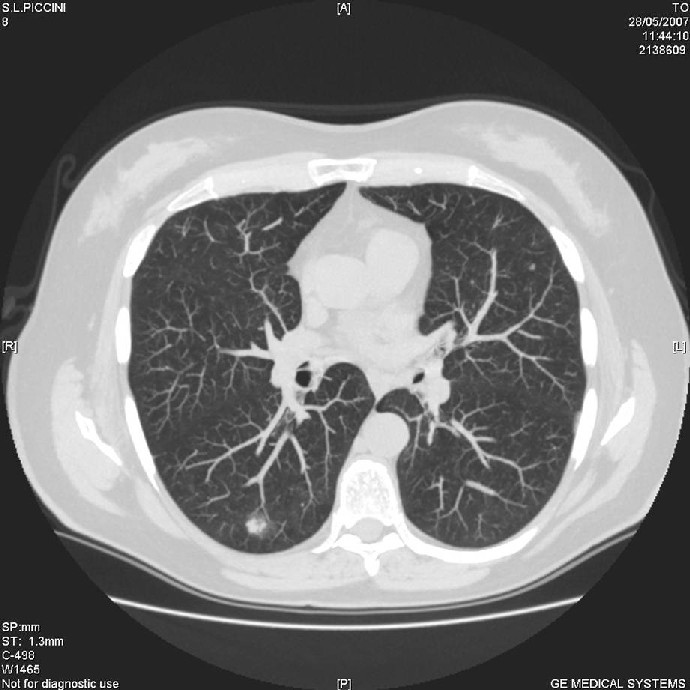

CT thorax